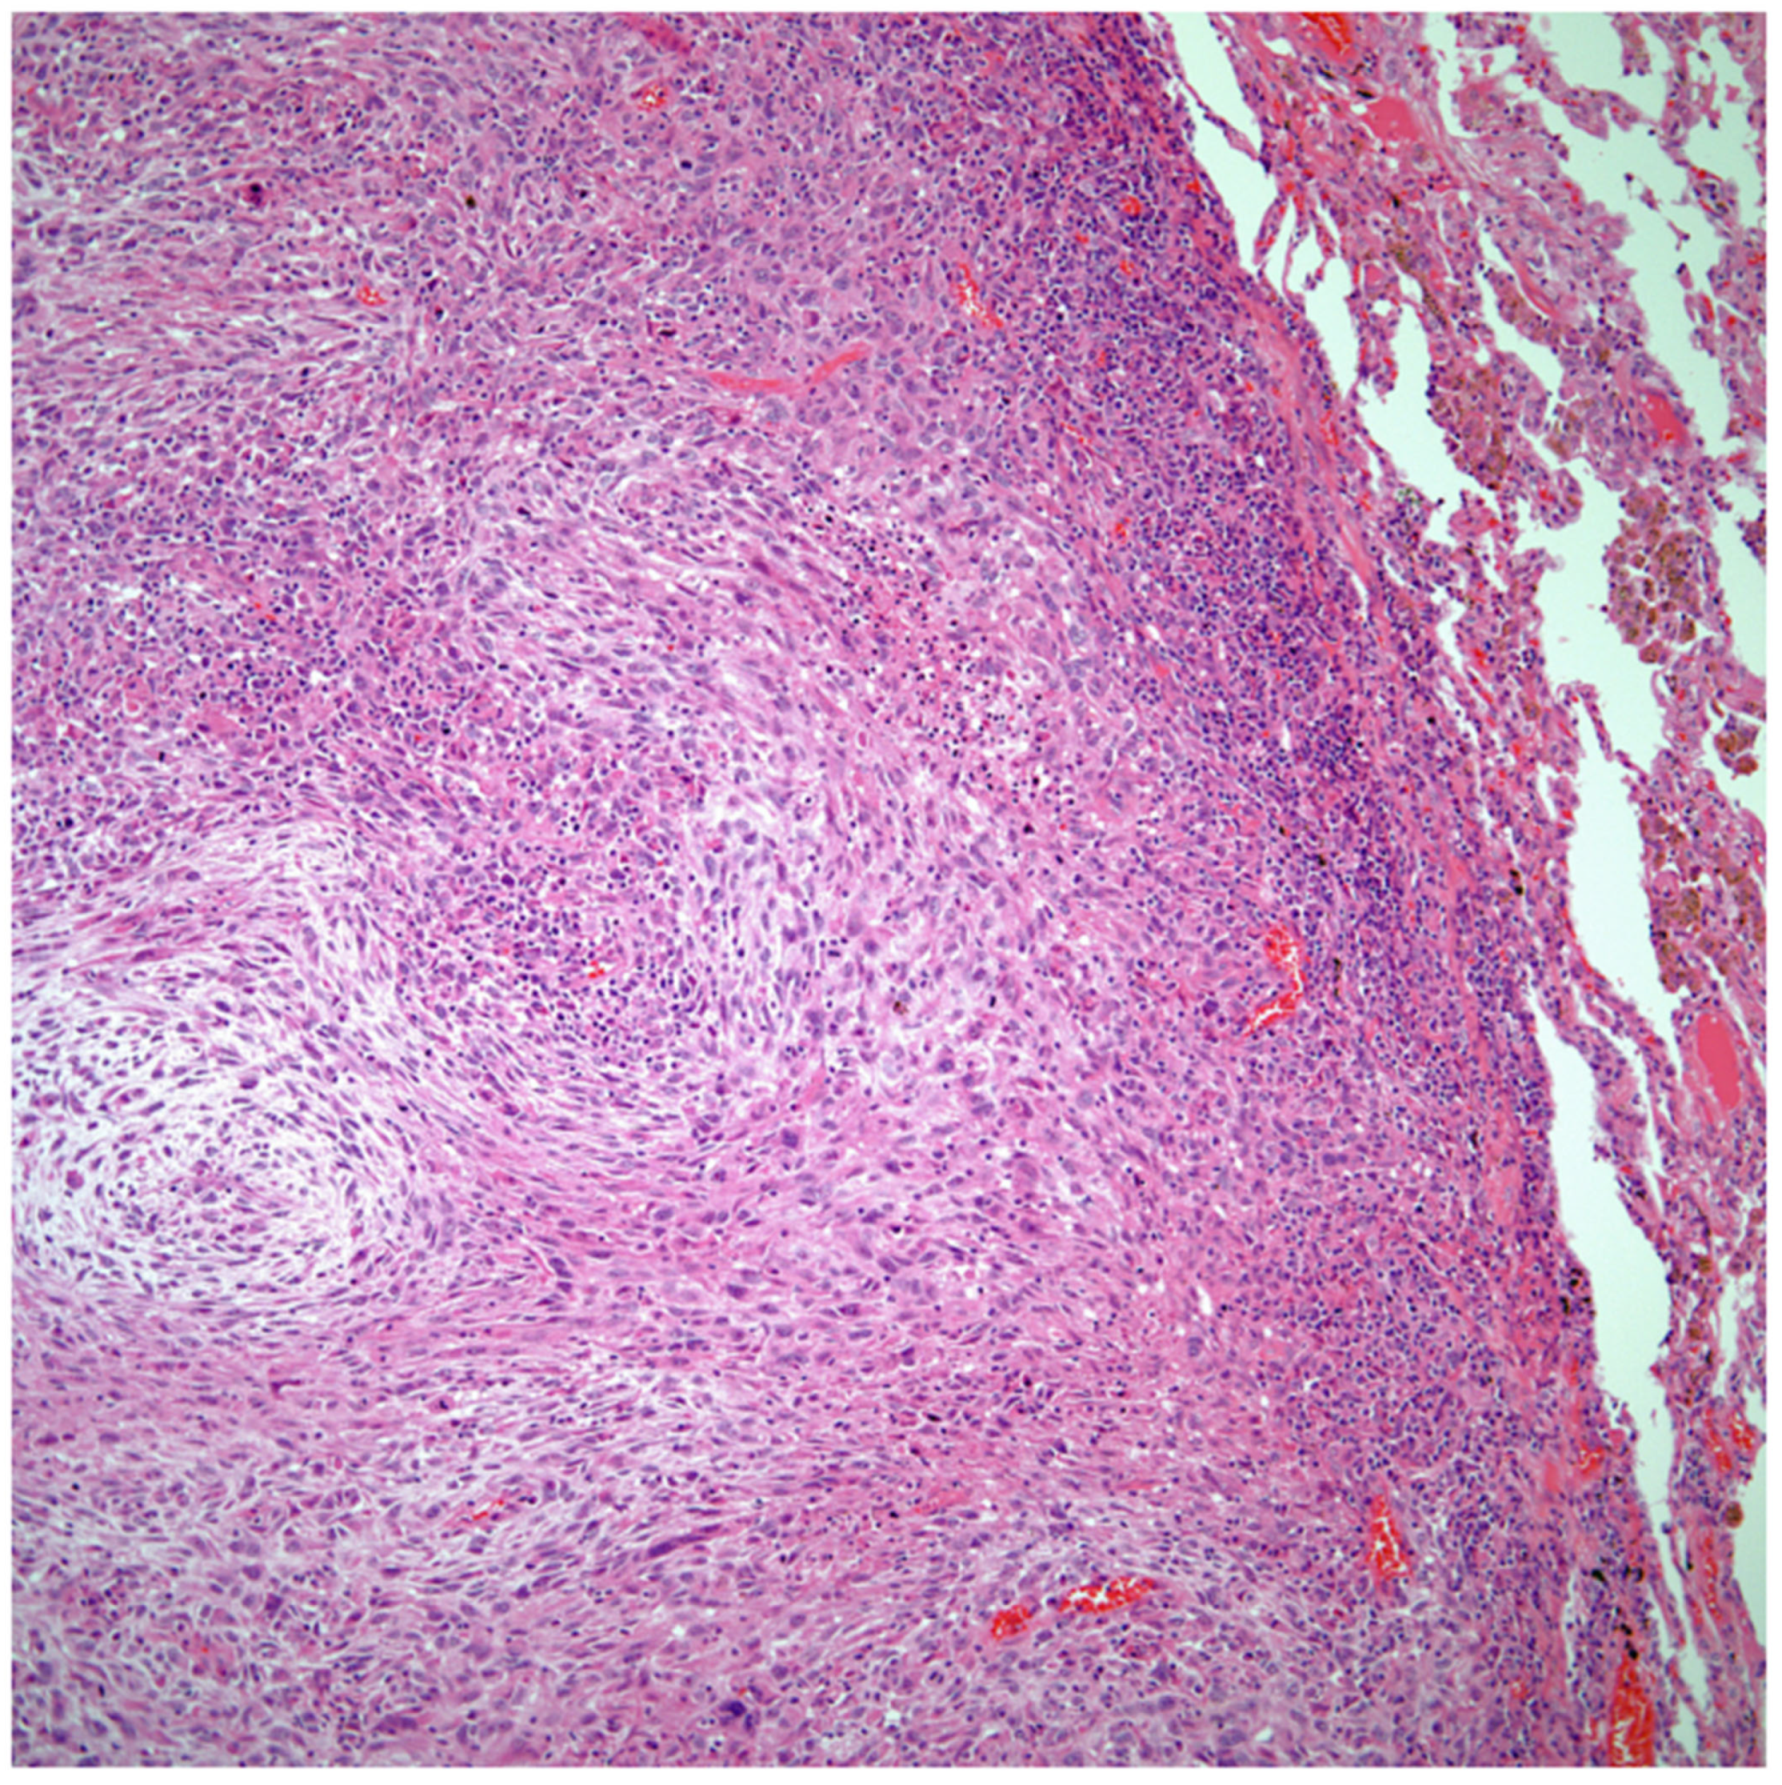

Sarcomatoid carcinomas: These tumors show a tightly packed spindle cell proliferation composed of slender cells with fusiform nuclei and inconspicuous nucleoli, replacing normal lung parenchyma. The tumors are well delimited but not encapsulated (Figure 1). Cellular atypia is variable and may show areas of mild to moderate to marked atypia. Mitotic figures also vary and may be inconspicuous or may be evident with the presence of atypical mitotic figures (Figure 2A,B). In high-grade tumors, the presence of necrosis and hemorrhage is prominent and is mixed with the neoplastic component. Important to recognize is that sarcomatoid carcinomas may be associated with areas of otherwise conventional non-small cell carcinoma such as adenocarcinoma or squamous cell carcinoma (Figure 3A,B). In addition, sarcomatoid carcinoma may also show the presence of bizarre giant cells admixed with the spindle cell component (pleomorphic carcinoma) (Figure 4).

Figure 2.

(A) Atypia and mitotic activity. (B) Neoplastic spindle cell proliferation.

Figure 3.

(A) Sarcomatoid carcinoma associated with areas of conventional adenocarcinoma; (B) Sarcomatoid carcinoma associated with areas of squamous carcinoma.